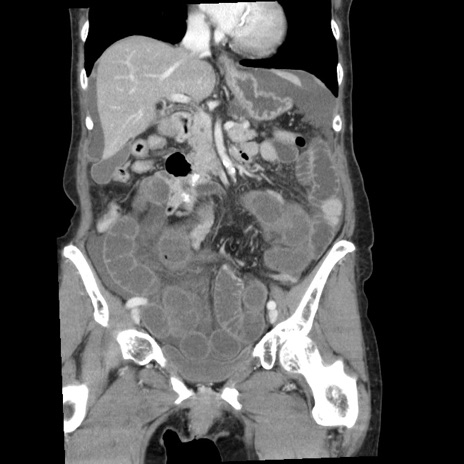

症例1(冠状断像)

【症例】80歳代女性

【主訴】腹痛

【現病歴】8時間前から腹痛あり来院。

【既往歴】糖尿病、脂質異常症、子宮体癌にて子宮全摘術

【身体所見】意識清明・会話良好だが腹痛で苦悶様、全腹部にわたって反跳痛と圧痛あり

【データ】WBC 13600、CRP 0.14、LDH 224、CK 90